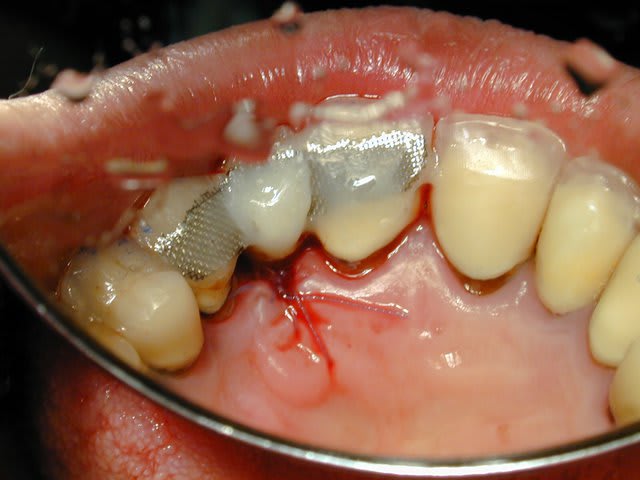

mis à part le liseret gris du collet suis content du résultat et pourtant c'était pas gagné d'avance : pas de GA ou peu et nécessité de faire une rog

donc la EII et ROG (nanobone + collagene +prf)

pas de MCI

à la réouverture déplacement en vestibulaire de la GA palatine pour redonner du "volume"

J'ai copié ta méthode à grille: vachement bien.